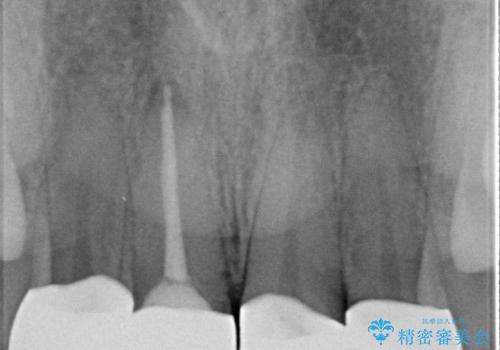

- 他院で治療した前歯の色が気になるということで来院された患者様です。前歯に色の差があり、レントゲンから内部にう蝕も見られたため、審美性に優れ、う蝕になりにくいオールセラミッククラウンで治療いたしました。

清掃性も上がったおかげで、歯肉の状態も良好に保てています。

色の調和もとれたので非常に満足いただけました。